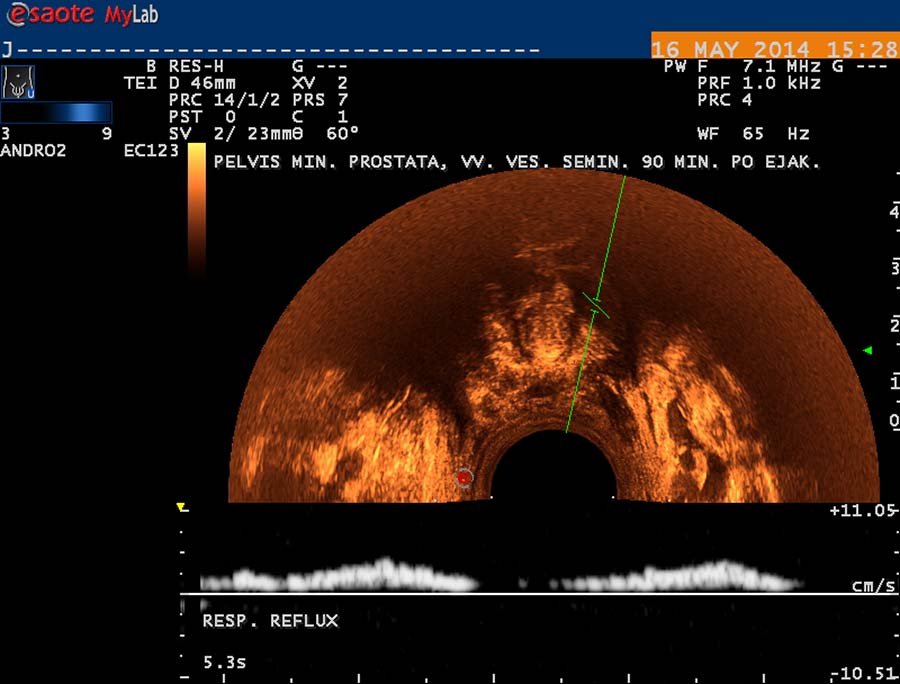

V případě druhém jde o kompresi ilických žil, které drénují vény z varlat probíhající podél chámovodů, a vény kremasterické, ústící do pánevních žilních pletení. Průběh žilní je však interindividuálně variabilní. Pleteň žilní pod bazí močového měchýře a okolo prostaty ( plexus venosus - labyrinthus Santorini) je velmi dobře vyšetřitelná transrektální USG. Používáme sondu o frekvenci 9 MHz se stejnými možnostmi harmonického zobrazení a Dopplerovské diagnostiky jako při vyšetření testes. Vény v okolí prostaty jsou dobře patrné v transverzální projekci na obr. 28, jejich ventrokaudální konvergence před prostatu je patrná na obr. 29, subprostatický průběh žil na obr. 30. Respirační reflux do těchto pletení je patrný na duplexním Dopplerovském záznamu – obr. 31, reflux v inspiriu a odtok v exspiriu na obr. 32. V kolmé projekci je patrný reflux při klidovém dýchání a při hlubším inspiriu na obr. 33. Přínos této diagnostiky pánevní žilní hypertenze bude v budoucnu užitečný při hodnocení žilní drenáže prostaty a žilní hypertenze v oblasti plexus venosus Santorini v souvislosti s významem hladin testosteronu a dihydrotestosteronu pro prostatu. Hladiny androgenů jsou v drenážní oblasti spermatických vén vyšší, nežli v periferní krvi.

obr. 31

obr. 32

obr. 33